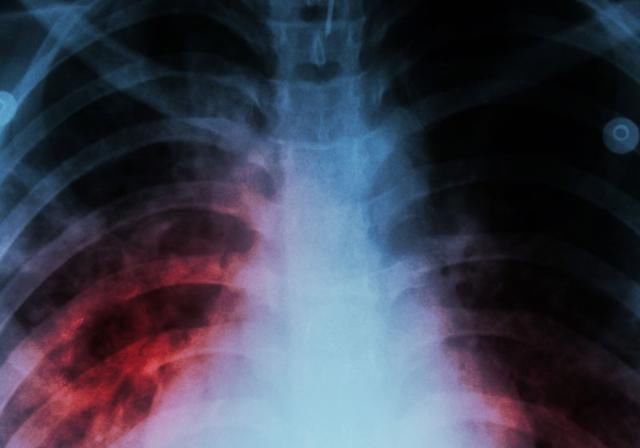

体检查出了肺结节,有可能是肺癌发出的警告。因为部分肺结节存在恶化这种情况,有可能在确定肺结节之后通过性质的判断发现有癌细胞存在,这种情况说明具备了肺癌的趋势,应该通过积极配合治疗的方式来控制疾病发展,避免肺癌出现。当然也并非所有的肺结节都是肺癌,病人应该根据结节的性质以及具体情况综合判断。

有部分情况下的肺结节其实并不需要担心,特别是体积非常小,而且经过长时间的观察并没有特殊改变的肺结节,这种情况性质稳定,而且也没有恶化这种趋势,可以排除成为肺癌的可能。

部分情况的肺结节没有癌变的表现,不需要太过紧张,特别是那些结节表面较光滑,没有周围模糊,出现特殊形状的结节,这种情况出现恶化的可能性较低。

一般具备恶化特点的肺结节形状都比较特殊,而且结节的边缘会出现模糊或者形状的改变。身体没有这种情况,肺结节边缘光滑,而且性质稳定,保守处理即可。

由此可见,体检出了肺结节确实有可能是肺癌,但是要判断其性质,还应该综合结节的形态、性质等进行判断,不要过度紧张,否则检查出了肺结节过度担忧,可能会带来其他方面的影响。值得一提的是,如果发现肺结节是肺癌引起,病人需要马上治疗,早治疗预后良好,可以通过手术的方式切除病灶,术后身体护理工作过好,可以避免肺部功能持续下降带来伤害。